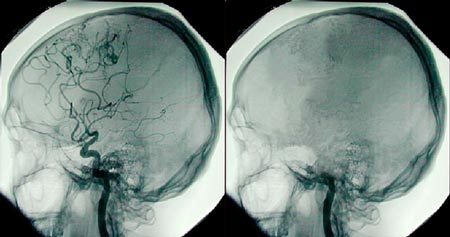

Đôi khi dùng điện não đồ (EEG), chẩn đoán hình ảnh mạch não, hoặc cả hai

Đôi khi EEG hoặc các xét nghiệm đánh giá tưới máu não được sử dụng để khẳng định sự vắng mặt của hoạt động não hoặc dòng máu não. Nhờ đó, cung cấp thêm bằng chứng cho các thành viên trong gia đình, nhưng các xét nghiệm này không phải lúc nào cũng được yêu cầu. Chúng được chỉ định khi không dung nạp được trắc nghiệm ngưng thở về mặt huyết động và mong muốn chỉ khám thần kinh một lần (ví dụ, nhằm đẩy nhanh việc lấy phủ tạng để cấy ghép